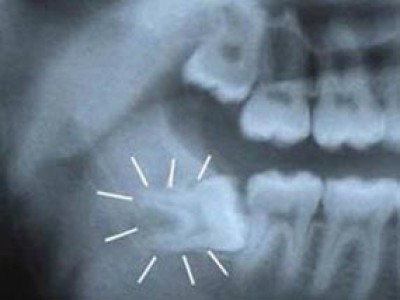

3. Huỷ hoại xương và răng xung quanh

Khi răng khôn mọc đâm sang răng bên cạnh, nó sẽ làm răng đó bị tiêu huỷ, lung lay, nhiều khi gây sâu răng, và cuối cùng là rụng răng. Triệu chứng sớm của việc mọc lệch này là những cơn đau âm ỉ ở khu vực đó.